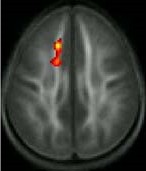

The area where the white matter quality increased (red/yellow area) among poor readers who received the remedial reading instruction. Source: Timothy Keller, Ph.D.; Marcel Just, Ph.D.

At the outset of the study, poor readers showed lower quality white matter than average readers in a brain region called the anterior left centrum semiovale. Six months later, at the completion of the intensive training, the poor readers showed significant increases in the quality of this region. Children who did not receive the training did not show this increase, suggesting that the changes seen in the remedial training group were not due to natural maturation of the brain.